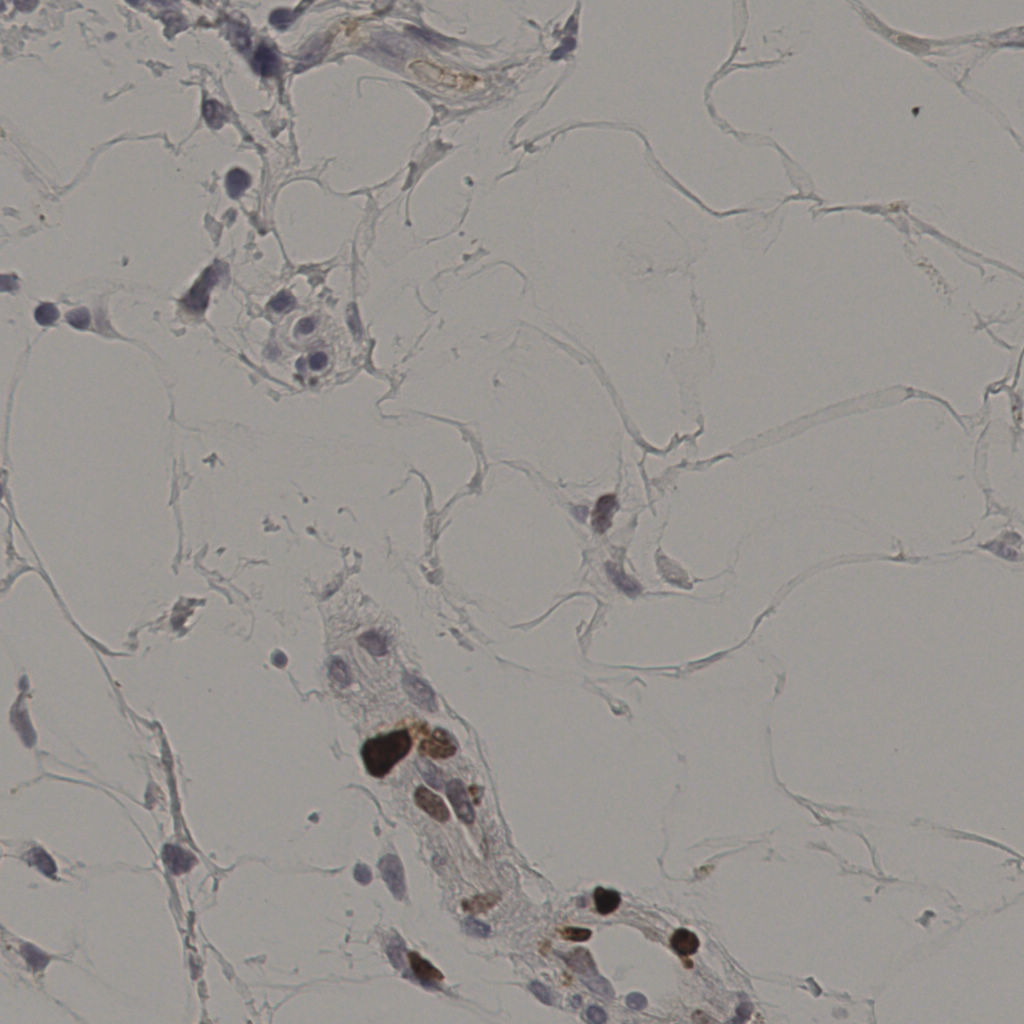

状态 处理完成

上传 2026-04-09 21:03

耗时 3796秒